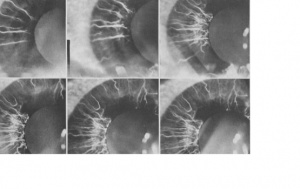

Iris angiograms performed during acute attacks demonstrate segmental iris ischemia, vascular congestion, and vessel leakage. Interestingly, in one case series, iris angiograms performed during the “prodromal phase” when IOP was not elevated also demonstrated focal iris ischemia.[13]

Posner and Schlossman first postulated that glaucomatocyclitic crisis was a result of autonomic dysregulation. They noted that 4 patients in their original 1948 case series also had a history of migraines.[1] In 1977, Raita and Vannas performed iris angiograms on a series of PSS patients; they found that not only was there focal iris ischemia during attacks but also ischemia during the prodromal normotensive phase.[13]